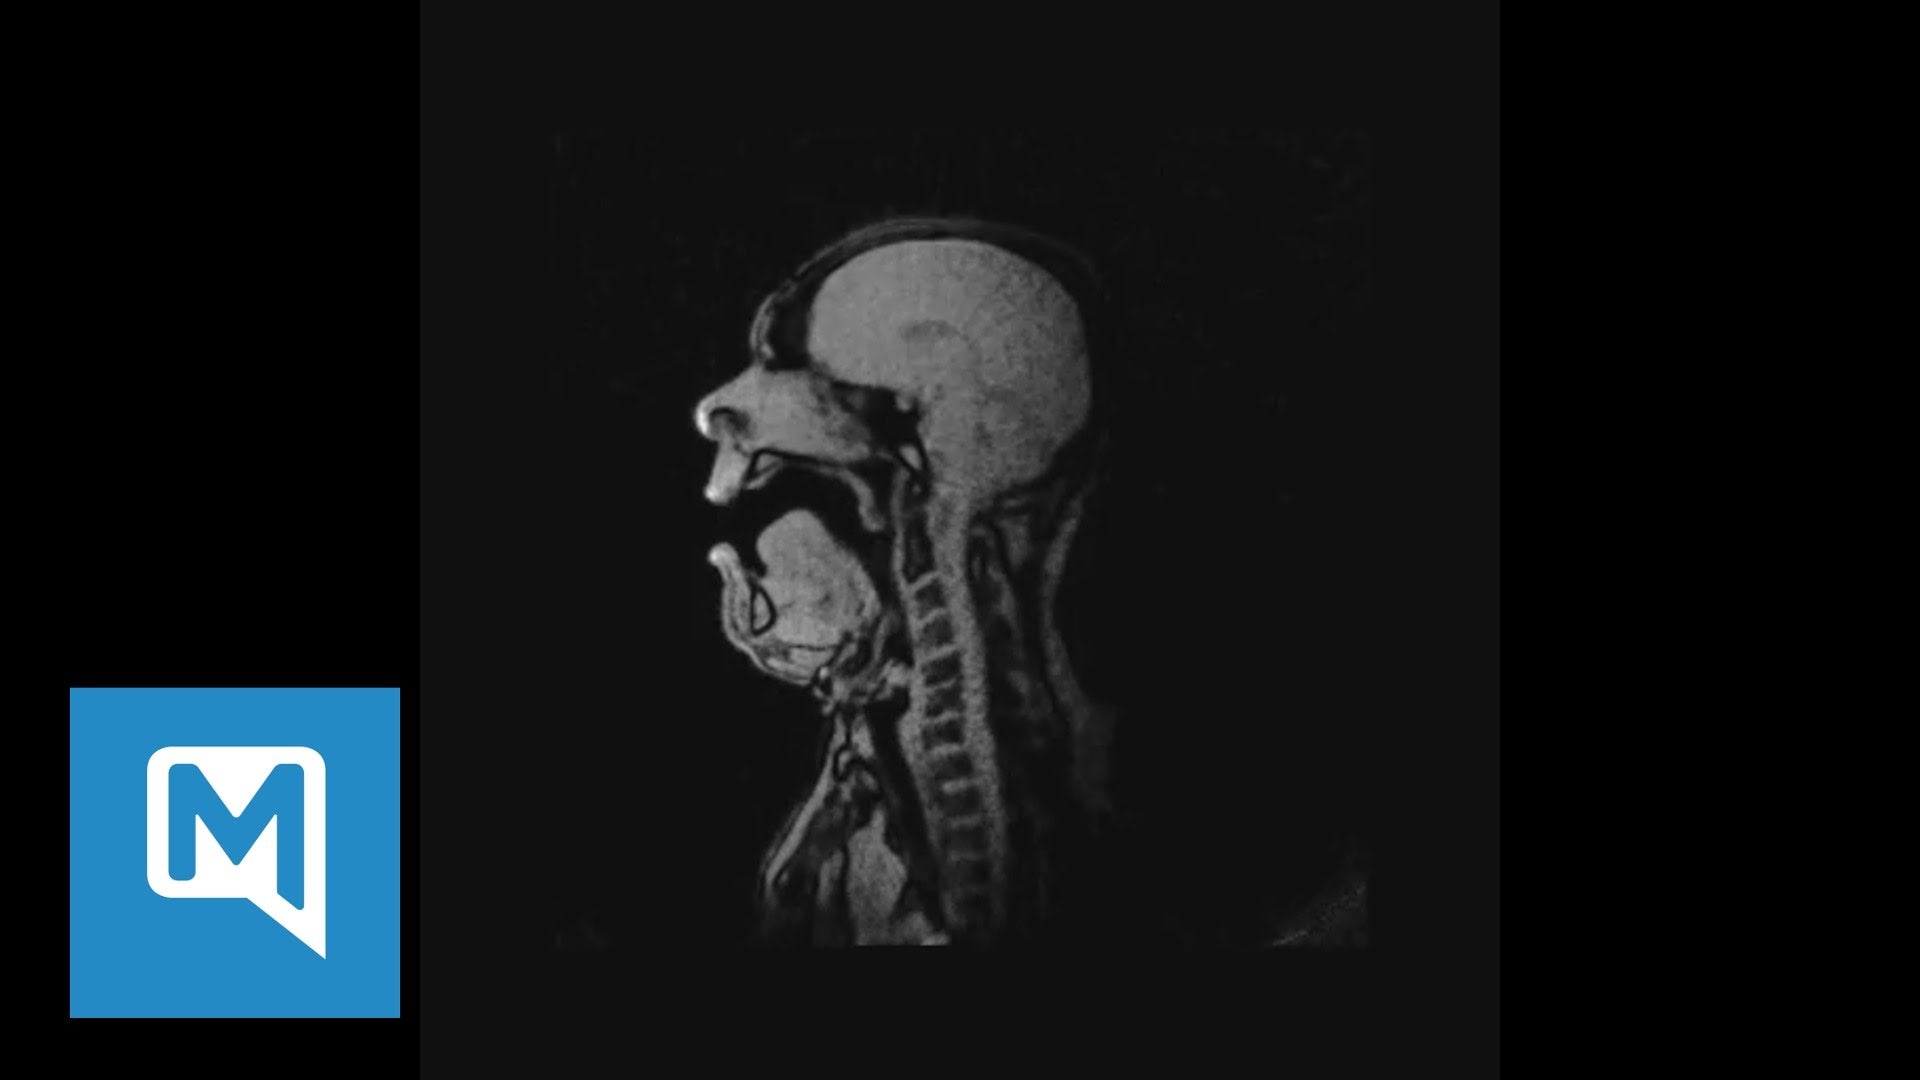

For a never-before-seen look at how an opera singer is able to produce such an amazing sound, German baritone Michael Volle performed Song to the Evening Star from Wagner’s Tannhäuser during an MRI scan. The technique uses magnetic fields and radio waves to see right through the human body, and is able to capture movement resulting in this fascinating, but freaky footage.